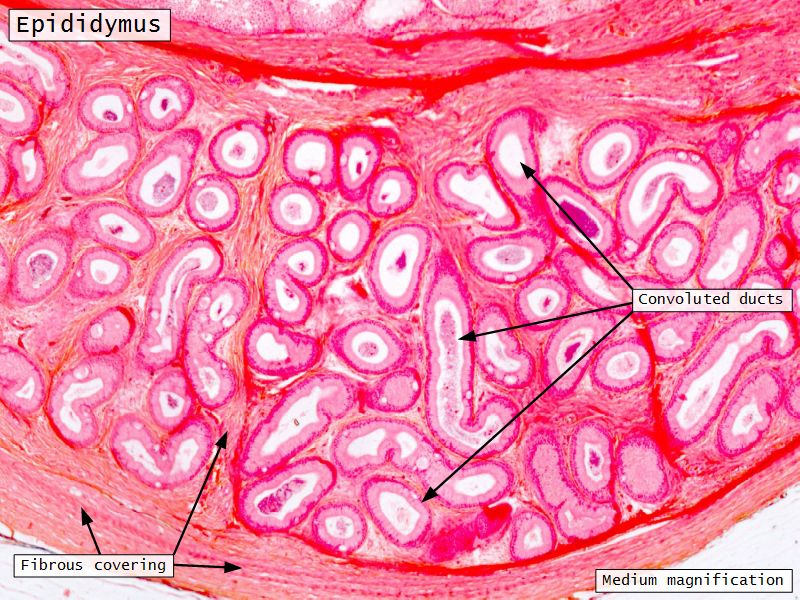

Epididymus

- Long convoluted duct

- With fibrous covering

- Inside visceral layer of tunica vaginalis testis

Epididymus

- Simple ciliated columnar epithelium

- Tall ciliated cells

- Elongated nuclei away from BM

- Low absorptive cells

- Spherical nuclei close to BM

- Surrounded circular smooth muscle